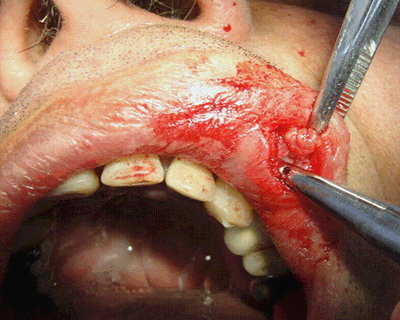

The emergency room diagnosis was a severe case of myiasis infestation. Clinical examination revealed edema of the upper lip with a small opening (required for the larvae to breathe). The patient reported the sensation of things moving inside the swollen area. After local anesthesia at the site of infection, an incision was made in the upper lip (Fig1) and the larvae were removed surgically (Fig2). Two 6 mg ivermectin tablets were prescribed. Following the procedure the patient was hospitalized for medical care to address his underlying poor health (primarily severe under-nutrition). The larvae were subsequently submitted for parasitology testing which reported them to be D. hominis.

Figure 1: Surgical removal of larvae from upper lip.